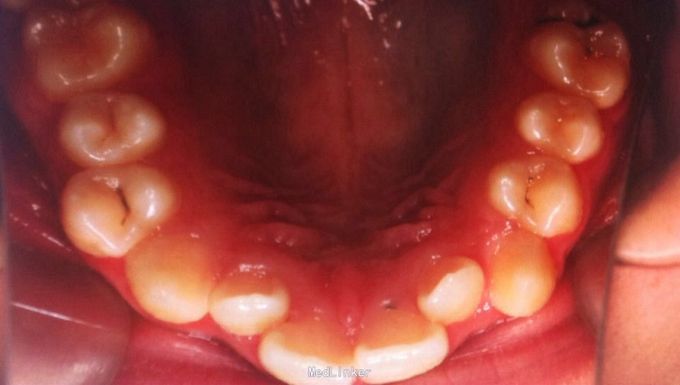

恒牙期 左右磨牙近中关系 12,22舌侧错位 32、33融合牙 右侧磨牙反合 上下牙列轻度拥挤 关节有弹响

安氏三类、后牙反合 不拔牙矫治,直丝弓矫治器,排齐整平上下牙列,解除后牙反合,矫治后覆合覆盖正常,磨牙中性关系,维持现有面型